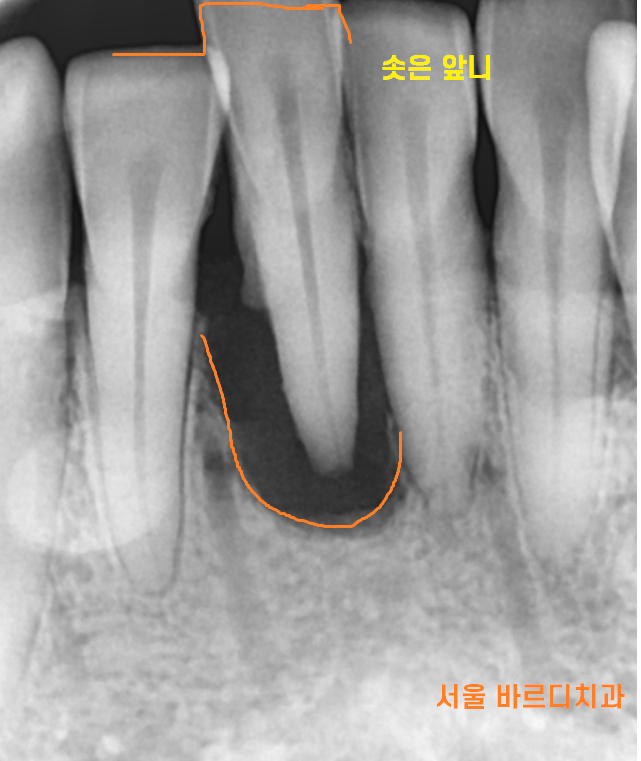

문제는 치아 잇몸뼈가 너무 녹아서...

뼈가 없었습니다.

임플란트 중에서는 앞니가 어려운 이유는

1)잇몸뼈가 얇기도 하면서

2)심미적인것

두개 다 만족을 시켜야하기 때문에 어렵습니다.

뼈가 너무 없어서

좁은 뼈에도 시술 할 수 있기에

이 제품을 사용했습니다.